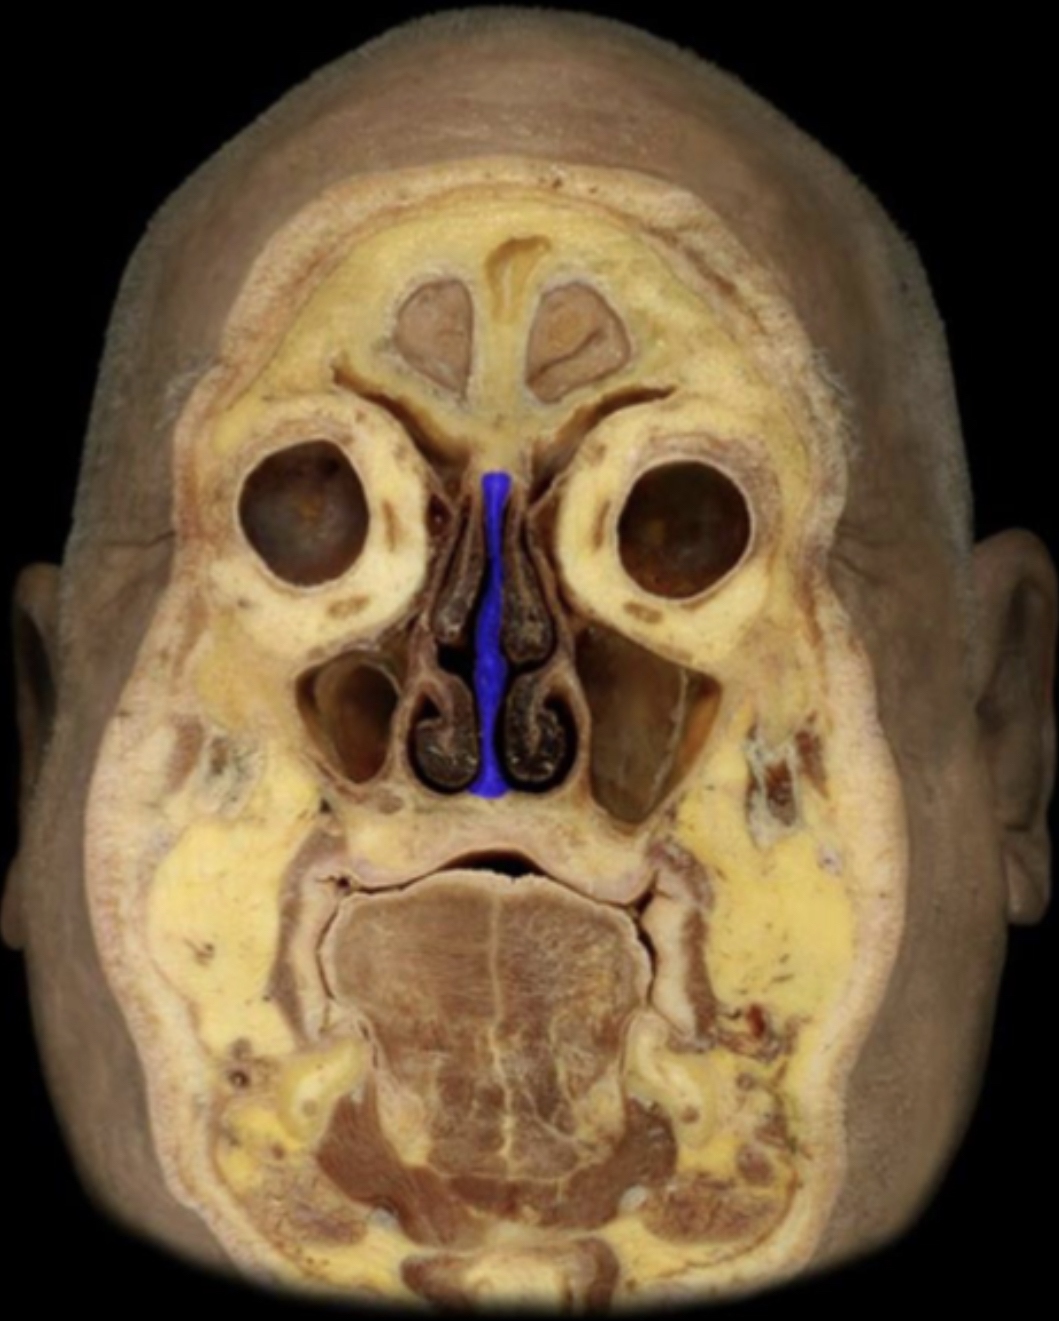

What structure is highlighted in blue?

External naris

Nasal cavity

Nasal septum